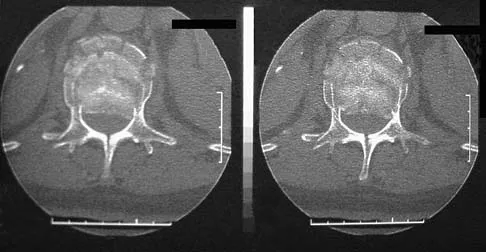

A 42-year-old man sustained a burst fracture at L2 in a motor vehicle accident. Examination reveals that he is neurologically intact. Figure 18 shows a cross-sectional CT scan through the fracture. If the fracture is managed nonsurgically for the next 2 years, the retained fragments can be expected to

Explanation